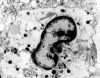

An autopsy limited to the brain was performed. The followings are representative photographs of the brain:

I. Semithin |

J. Semithin |

K. |